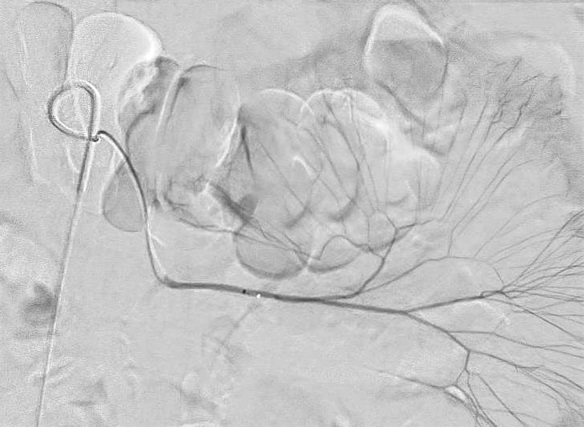

glue 0.1ml 注射后 |

出血停止,并完全恢复

CT一个月后:无肠缺血,仍然可见胶滞留在肠壁上